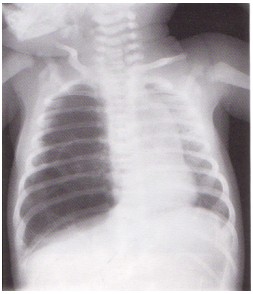

pneumothorax.jpg